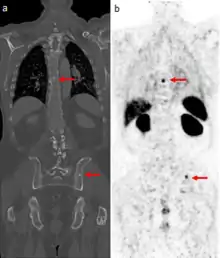

Gallium DOTA scans

68Ga DOTA conjugated peptides (including 68Ga DOTA-TATE, DOTA-TOC and DOTA-NOC) are used in positron emission tomography (PET) imaging of neuroendocrine tumours (NETs). The scan is similar to the SPECT octreotide scan in that an octreotide-based somatostatin analogue (such as edotreotide) is used as the radioligand, and there are similar indications and uses as ocreotide scans, however image quality is significantly improved.[35] Somatostatin receptors are overexpressed in many NETs, so that the 68Ga DOTA conjugated peptide is preferentially taken up in these locations, and visualised on the scan.[36] As well as diagnosis and staging of NETs, 68Ga DOTA conjugated peptide imaging may be used for planning and dosimetry in preparation for lutetium-177 or yttrium-90 DOTA therapy.[37][38]